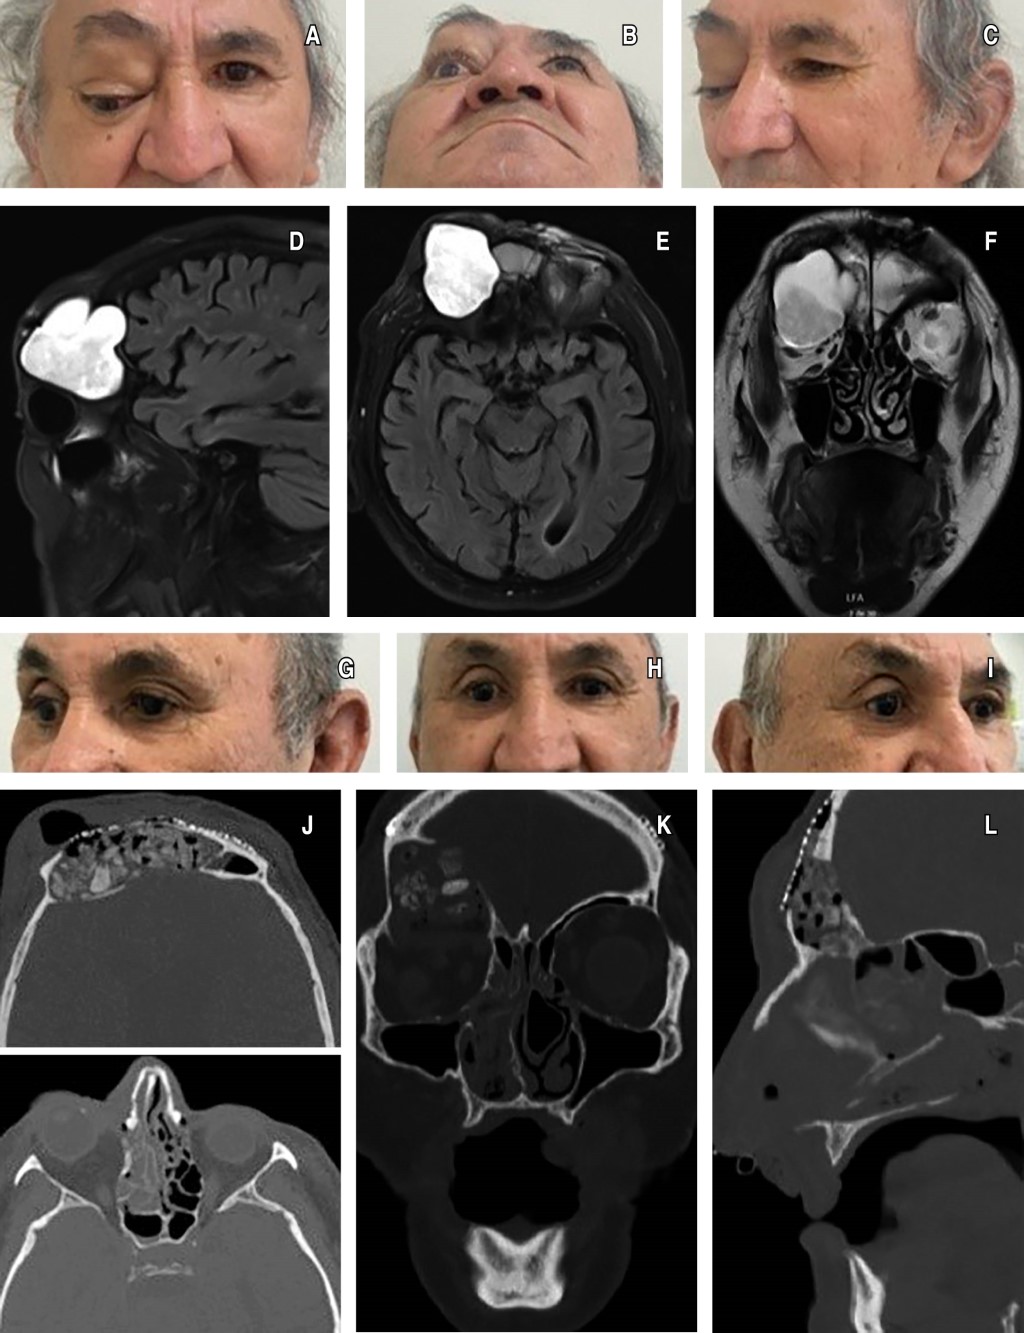

Catorce años después consulta por aumento de volumen en la región supraciliar derecha y amaurosis en el ojo derecho (Figura 1A a 1C). La resonancia magnética (RM), revela una masa de partes blandas en el seno frontal derecho, con dimensiones de 52 × 74 × 33 milímetros, además de un severo adelgazamiento de las tablas interna y externa y desplazamiento del globo ocular hacia caudal y anterior (Figura 1D a 1F). Se diagnostica mucocele en el seno frontal derecho.

INTERVENCIÓN QUIRÚRGICA

Se realizó la exéresis del mucocele frontoorbitario, la desfuncionalización del seno frontal bilateral y la obliteración del conducto frontonasal bilateral. Se posicionó un bloque de gelita en la zona supraorbitaria derecha y un colgajo perióstico en el seno frontal bilateral. Además, se realizó un aporte óseo con 60 mL de injerto óseo particulado, seguido de la colocación de una malla de osteosíntesis y el cierre del colgajo por planos.

SEGUIMIENTO

Once meses después de la cirugía, el paciente ha evolucionado favorablemente, sin presentar dolor ni sintomatología en cabeza y cuello. Además, se observa una evidente mejoría de la proptosis en el ojo derecho (Figura 1G a 1L).